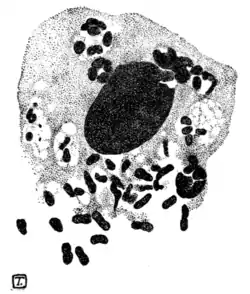

Fig. 93.—Parasitic elements in ulcerating granuloma of pudenda.

through the protoplasm of the affected cells; more often they are arranged in little round clusters of eight or ten. Recently de Souza Araujo and others in Brazil have confirmed and extended Donovan's discovery. The Calymmatobacterium granulomatis, as they term the germ, is capsulated, non-motile, Gram-negative, non-spore-forming, does not liquefy gelatin nor coagulate milk. Under cultivation it is polymorphic, occurring as cocci, diplococci, bacilli, diplobacilli, and filaments, all forms possessing a

mucous capsule. It retains its virulence in experimental animals as far at least as the hundredth sub-culture on gelatin. In sections of the affected tissues the bacteria are seen to lie both inside and between the cells as capsulated cocci or diplococci, in chains or in zooglœa masses.